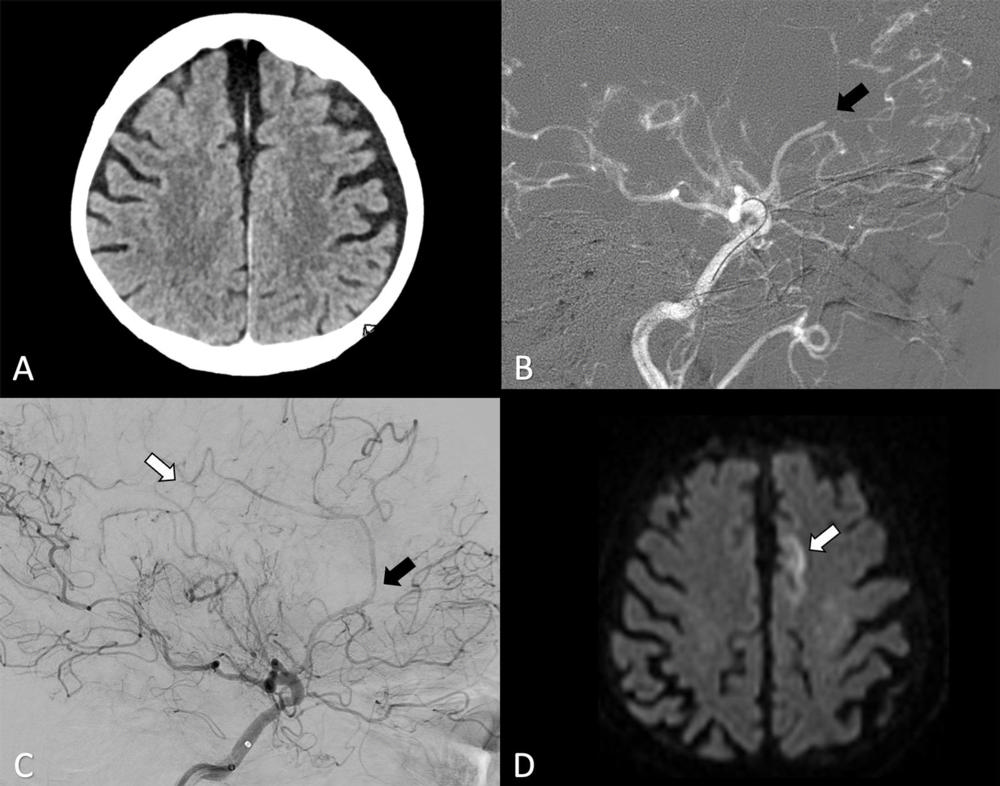

Figure 3. (A) Axial contrast-unenhanced CT image at admission shows no sign of early ischemic changes. (B) Digital subtraction angiography shows a proximal occlusion of the A3 segment (arrow, sagittal view). (C) After two thrombectomy attempts the affected territory underwent partial reperfusion (black arrow, sagittal view) with a distal remaining A5 occlusion (white arrow, sagittal view). (D) Follow-up with MRI at 24 hours shows signs of infarction in the distal territory of the anterior cerebral artery on axial diffusion-weighted image (arrow).